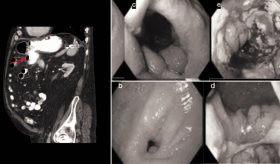

La Enfermedad Inflamatoria Intestinal (EII) es un término que abarca dos condiciones principales: la colitis ulcerosa y la enfermedad de Crohn. Ambas condiciones se caracterizan por la inflamación crónica del tracto digestivo y se consideran enfermedades autoinmunes, donde el sistema inmunológico del cuerpo ataca erróneamente los tejidos sanos del tracto digestivo.

En ocasiones, es difícil distinguir entre estas dos condiciones, y algunos pacientes pueden cambiar de un diagnóstico a otro con el tiempo.

Los síntomas comunes de la EII incluyen pérdida de peso inexplicable, diarrea crónica, dolor abdominal, inflamación ocular, dolor en las articulaciones y, en algunos casos, cálculos renales.